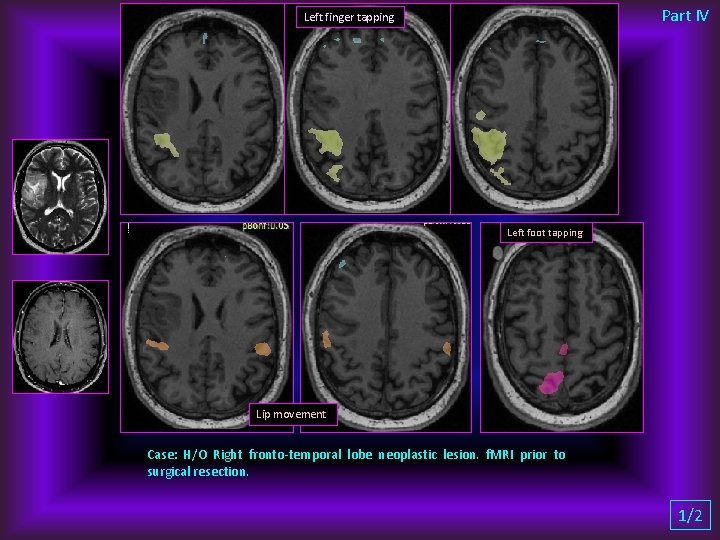

Part IV Left finger tapping Left foot tapping Lip movement Case: H/O Right fronto-temporal lobe neoplastic lesion. f. MRI prior to surgical resection. 1/2